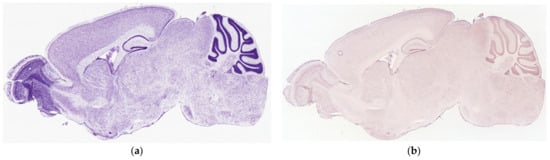

3.6. ISH Visualization of TAAR6 Expression in the Mouse Brain

The ISH expression data were mined from the Allen Brain Atlas: Mouse Brain as described in the Material and Methods section. Following the represented raw expression values and section images, TAAR6 was weakly expressed in all estimated brain regions.

The highest expression was shown in the murine olfactory bulb, which was not described in any other dataset included in the review. As in the RNAseq data, DRD2, ADRB2, and HTR1A expression levels were more pronounced than TAAR6 expression in all described structures (Figure 6).

Figure 6.

TAAR6 mRNA expression patterns in mouse brain, sagittal projection. (a) Nissl staining from the Allen Mouse Brain Atlas; (b) expression of the Taar6 gene in adult mouse brain identified by in situ hybridization in the Allen Mouse Brain Atlas (b and c in the same slice position); (c) expression of Taar6, Drd2, Adrb2, and Htr1a genes in the mouse brain, based on log10 data of expression from the Allen Mouse Brain Atlas. Data available at the Allen Mouse Brain Atlas, mouse.brain-map.org and atlas.brain-map.org. Nissl staining and TAAR6 riboprobe RP_050705_03_A11: https://mouse.brain-map.org/experiment/show/70724989 accessed on d16 March 2022; Adrb2 riboprobe RP_050208_01_A11, sagittal projection: https://mouse.brain-map.org/experiment/show/68744522 accessed on 16 March 2022; Drd2 riboprobe RP_Baylor_102735, sagittal projection: https://mouse.brain-map.org/experiment/show/358 accessed on 16 March 2022; Htr1a riboprobe RP_071018_03_D06, sagittal projection: https://mouse.brain-map.org/experiment/show/79394355 accessed on 16 March 2022.